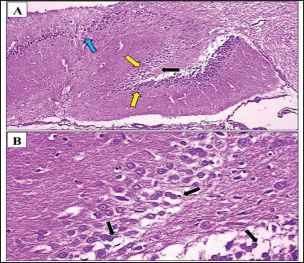

The Gum Arabic-treated group demonstrated notable improvement relative to the positive control group. Histological analysis (Fig. 3A,B) revealed less severe neurodegeneration, with a higher number of granule cells, suggesting a partial neuroprotective effect. Amyloid beta accumulation was reduced by approximately 50% in the Cornu Ammonis region compared with that in the negative control group (Fig. 4). Statistical analysis confirmed a significant (p < 0.05) increase in cell preservation in the Gum Arabic group compared with the Fenchol and memantine groups. In the Fenchol-treated group, histological assessment showed reduced granule cell density compared with the negative control, but with minimal amyloid beta deposition, particularly in the hippocampus, where plaques were nearly absent (Fig. 5A,B). The histogram in Figure 6 demonstrated a statistically significant (p < 0.05) protective effect in this group compared with both the Gum Arabic and memantine groups.

Fig. 3. Photomicrograph of the hippocampus of a Fenchol-treated rat. (A, B) Note the density of granule cells (yellow arrow) was lower in the negative control group than in the positive control group, likely due to neuronal loss in the dentate gyrus of the affected hippocampus. However, the number of granule cells was higher than that in the positive control and Arabic Gum groups. Also, mild neurodegeneration (black arrow) was observed in neurocyte of Cornu Ammonis region 2. H&E. A: 100x and B: 400x

Fig. 5. Photomicrograph of the hippocampus of rats treated with memantine. (A, B) The density of granule cells (yellow arrow) was lower in the negative control group than in the positive control group due to neuronal loss in the dentate gyrus of the affected hippocampus. However, the number of granule cells was higher than that in the positive control and Arabic Gum groups H&E. A: 100x and B: 400x.